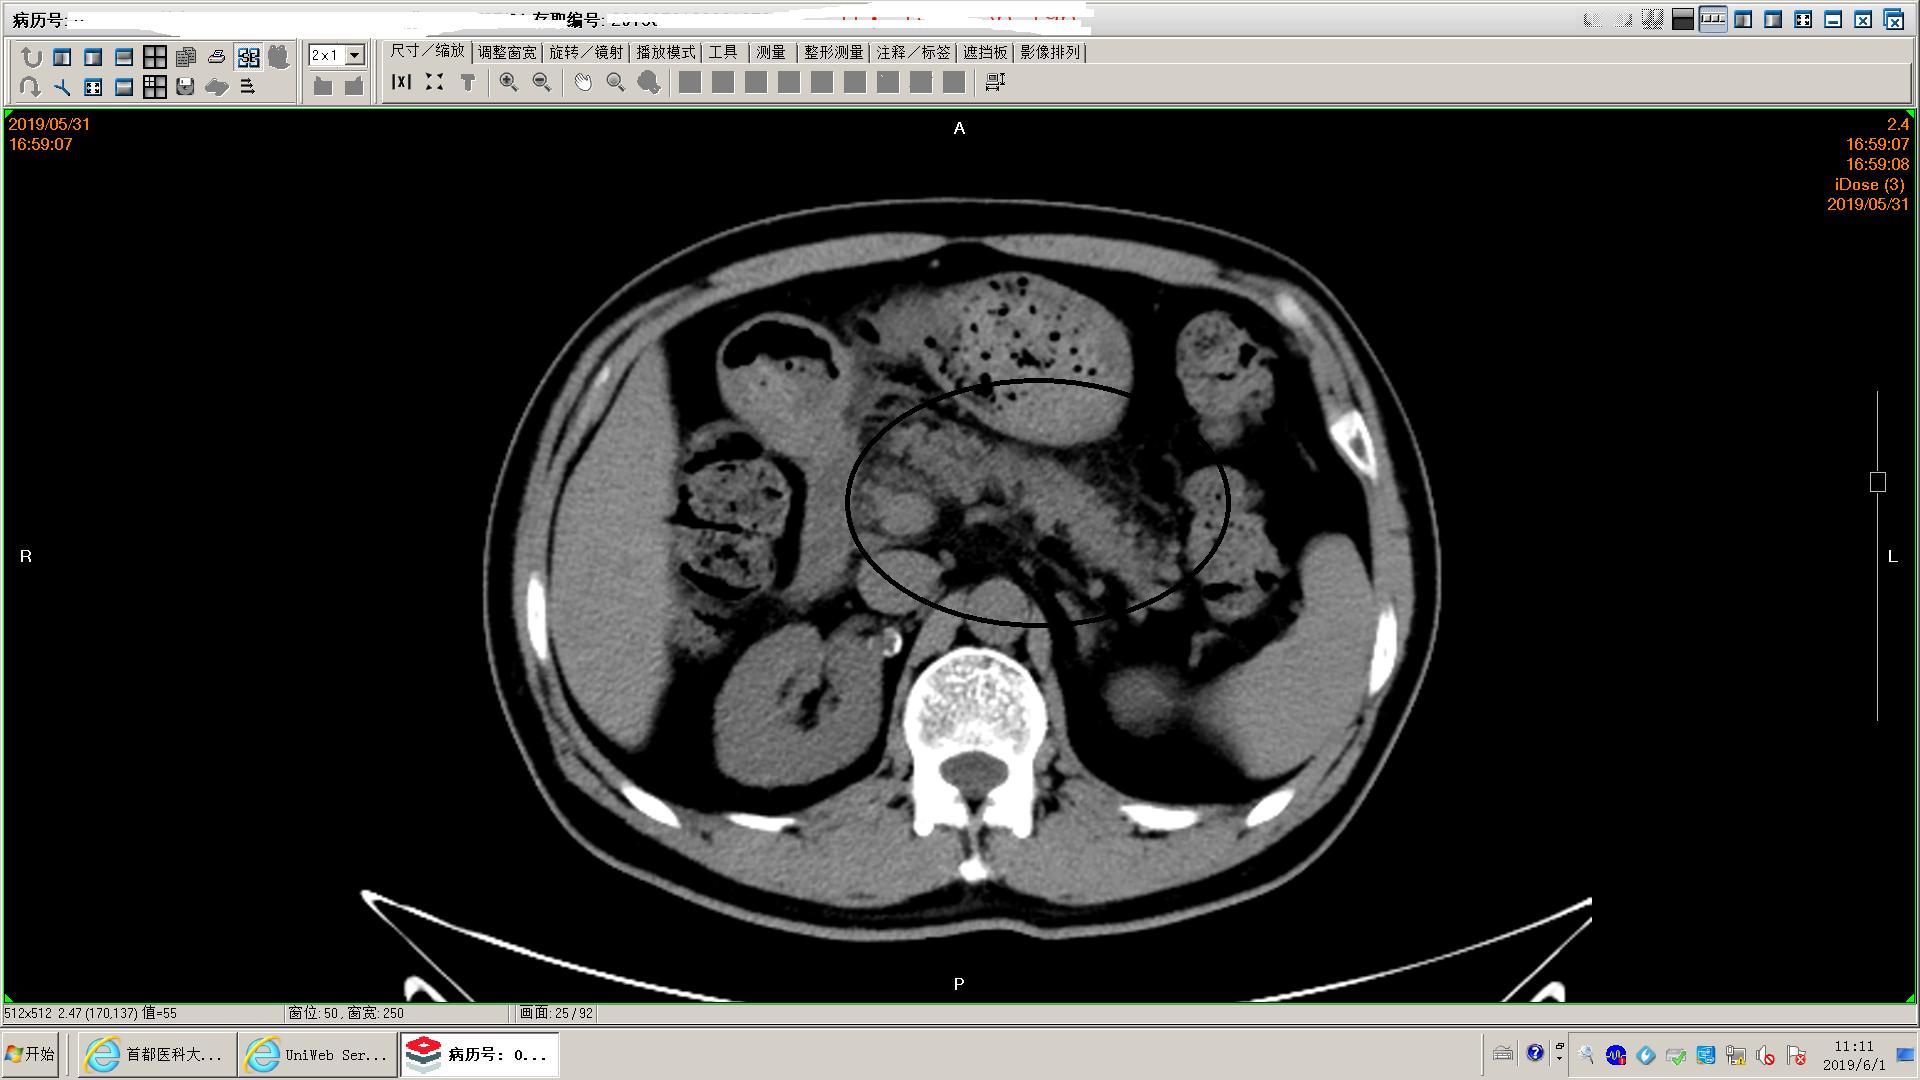

下面是一例胆源性胰腺炎影像学和化验表现,这个病人没有脏器功能不全,胰腺坏死不明显,周围没有明显积液,还不是重症胰腺炎。虽然有可疑胆管结石,但是没有黄疸,我们会在做核磁mrcp证实一下结石的位置。患者胃里面有一些残存的食物,我们会用胃管做胃肠减压,有助于胃肠道休息恢复;肠道里面积存的粪便也比较多,肠鸣音听不到,通过肥皂水灌肠促进肠道蠕动排除,有助于胃肠道功能恢复。然后给予生长抑素抑制胰酶分泌,禁食水补液,消炎治疗。

胃内有残余食物

肠道积存大量粪便